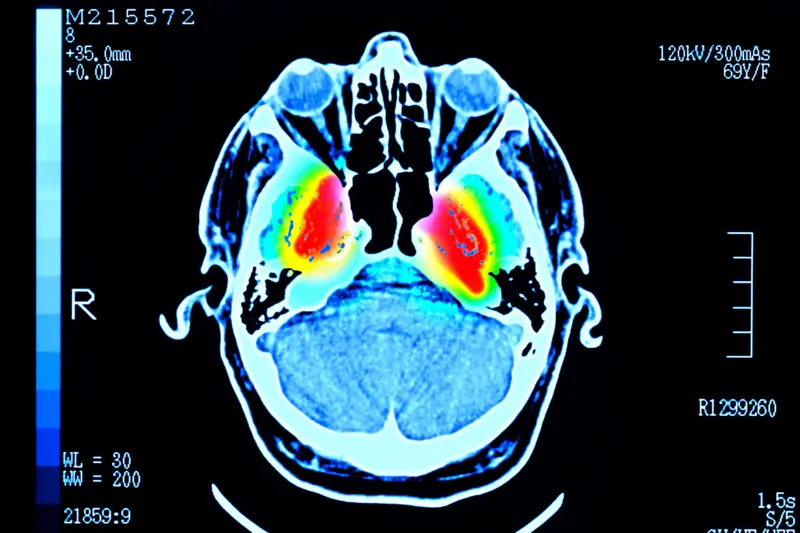

Um estudo publicado na revista Nature Communications identificou que o cérebro humano não se desenvolve de forma linear. Para esse estudo, cerca de 4 mil pessoas de até 90 anos fizeram exames que mostraram as conexões entre suas células cerebrais.

Já o envelhecimento tem início aos 66 anos e não ocorre de forma brusca, mas com mudanças nos padrões de conexão. O cérebro deixa de funcionar como um único conjunto integrado e passa a se dividir em regiões que trabalham de forma mais independente, como integrantes de uma banda que começam projetos solo.

Embora o estudo tenha analisado cérebros saudáveis, essa é também a idade em que surgem sinais de demência e hipertensão, que afetam a saúde cerebral.